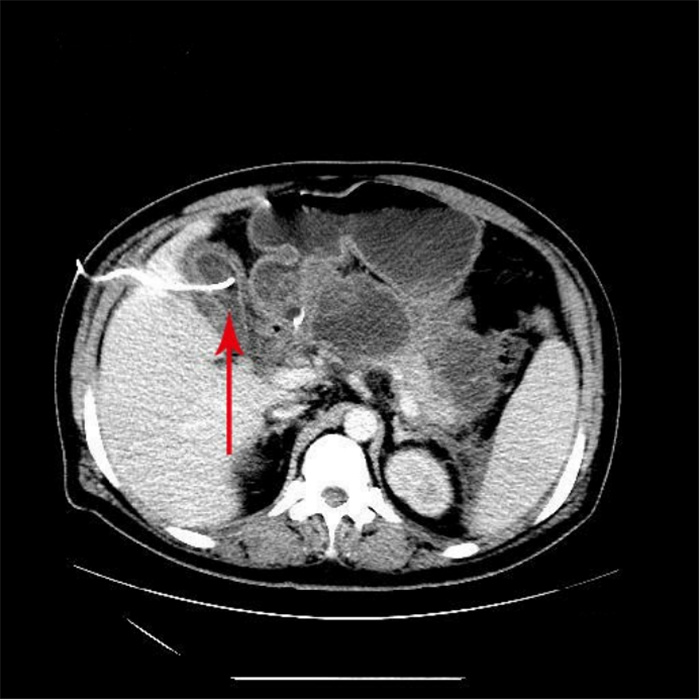

1 资料与方法患者吴某,男,33岁,身体质量指数37 kg/m2,因“腹痛13 h”急诊就诊。患者餐后出现上腹部持续性胀痛,向腰部放射,疼痛逐渐加重,急诊收住院。既往史:高血压病史2年,血压最高达200/100 mmHg(1 mmHg=0.133 kPa),未服用降压药。糖尿病病史1年,未行治疗。查体:体温36.6 ℃、脉搏130次/min、呼吸38次/min、血压228/113 mmHg,神志清楚,皮肤、巩膜无黄染,两肺未及干湿性啰音;心律齐,未闻及杂音,腹膨隆,腹肌紧张,上腹部压痛明显,无反跳痛,肠鸣音弱;肌力、肌张力正常,神经系统检查阴性。主动脉CTA:未见夹层;上腹部CT:AP(见图 1);心电图:窦性心动过速;肝胆脾彩超:重度脂肪肝,胆囊饱满,胰腺肿大并不均质改变。化验检查示,随机血糖32.8 mmol/L,动脉血气分析pH 7.313,二氧化碳分压23.8 mmHg,氧分压68.7 mmHg,标准碳酸氢根11.8 mmol/L,血氧饱和度93.5%,剩余碱-12.28 mmol/L(鼻导管吸氧FiO2 0.33),血乳酸12.6 mmol/l,总胆固醇12.61 mmol/L,甘油三酯23.31 mmol/L。血清钙1.56 mmol/L,凝血功能正常。血常规检查示,白细胞计数(WBC)14.08×109/L,中性粒细胞百分比(NE%)84.4%,红细胞数(RBC)5.73×1012/L,血红蛋白(HGB)194 g/L,红细胞压积(HCT)0.58,血小板数(PLT)410×109/L。肝功能检查示,丙氨酸氨基转移酶(ALT)、天冬氨酸氨基转移酶(AST)、r-谷氨酰转移酶(r-GT)、总胆红素(TBiL)、非结合胆红素(NCBiL)、结合胆红素(CBiL)均正常,总蛋白(TP)143 g/L,白蛋白(Alb)37.5 g/L。肾功能检查示,尿素氮(BUN)7.35 mmol/L,肌酐(Cr)296.8 μmol/L。尿液分析示,蛋白(Pro)3+,葡萄糖4+,酮体弱阳性,糖化血红蛋白9.3%,血淀粉酶2 320 U/L,尿淀粉酶22 073 U/L,脂肪酶382.80 mmol/L。患者入住急诊监护室8 h后胸闷、呼吸困难进行性加重,氧合指数 < 100,紧急行气管插管呼吸机辅助呼吸。

| 胰腺弥漫性增大,密度不均匀减低,周围间隙模糊并多发片絮状、索条状渗出影,胆囊不大,囊内未见明显异常密度影。 图 1 患者入院时腹部CT |